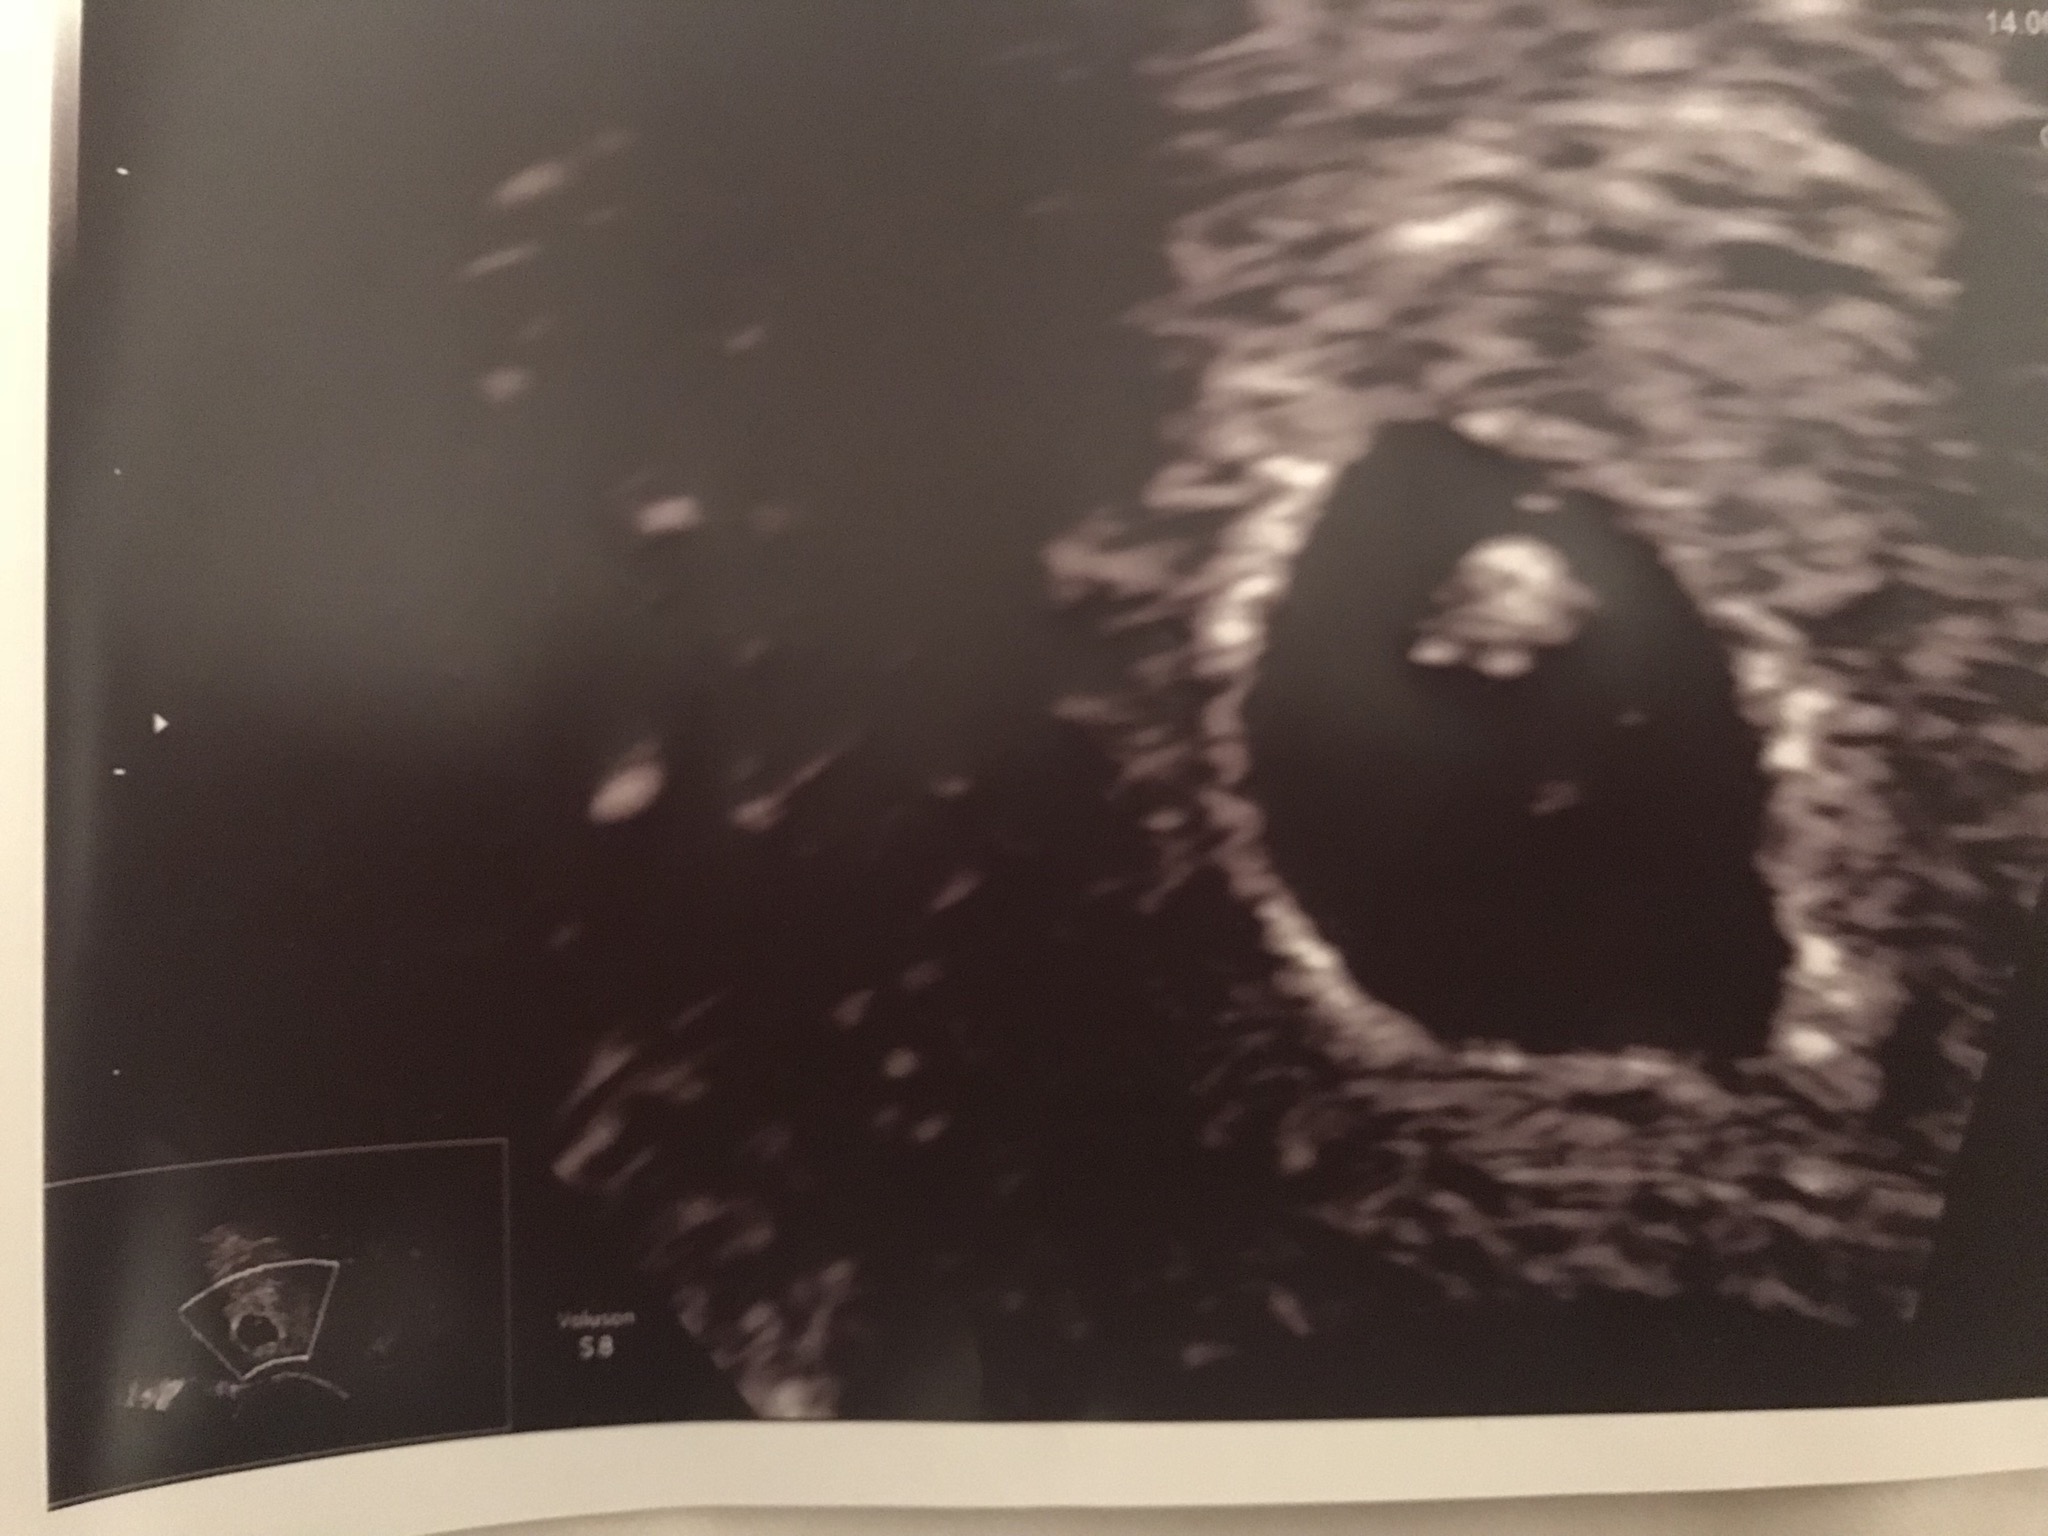

What do you think this little will be according to Ramzi?

I forgot to say it was vaginal ultrasound ☺️